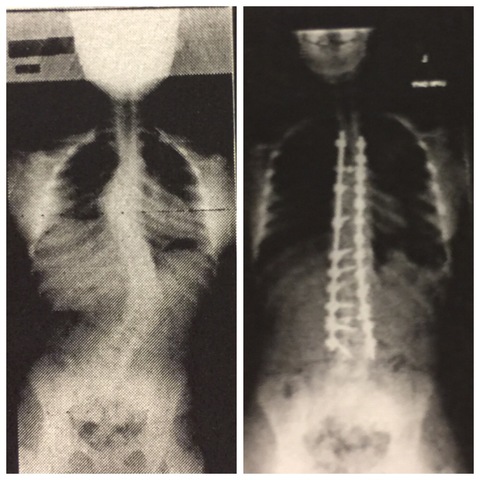

• Scoliosis

I was diagnosed with scoliosis in the beginning of summer before my eighth grade year. Upon multiple doctor's appointments we were informed that my spinal curve was so severe that I was in need of corrective surgery. It was scheduled for two weeks into my eighth grade year. I was taken out of school for four months on home bound. I was behind in my studies due to this, and it took me quite some time to catch up to other students.